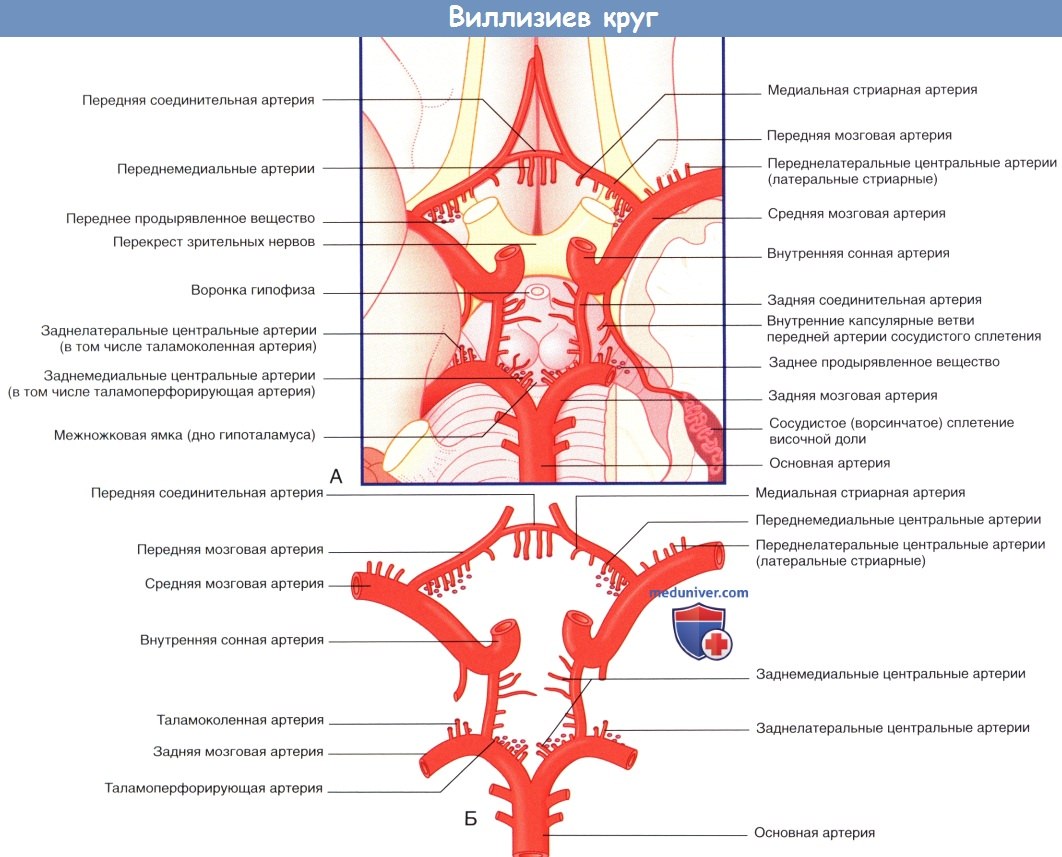

Особенности и диагностика левостороннего кровотока